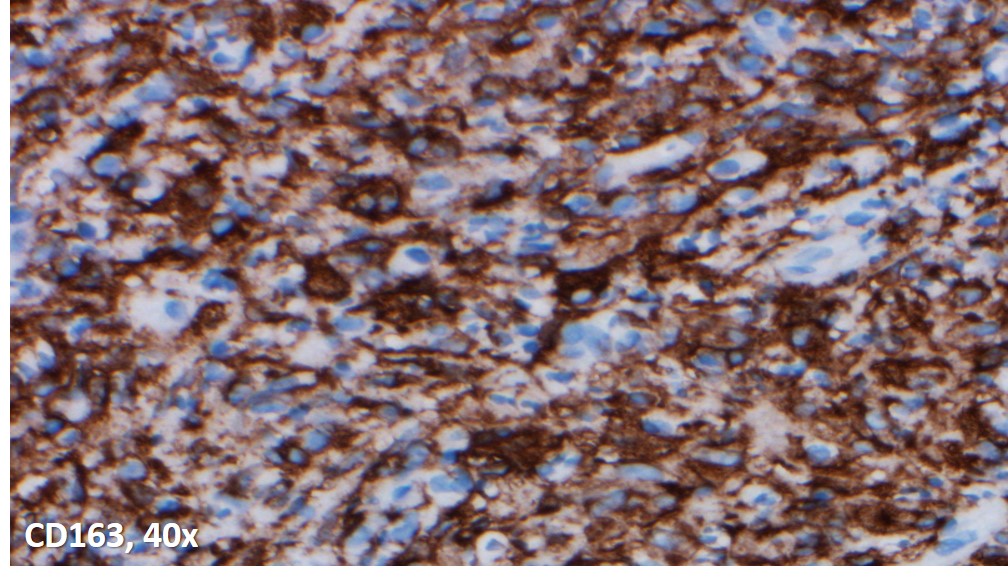

Immunoperoxidase and special stains were performed on this case. The cells were diffusely positive for CD45 and CD163, and negative for keratin cocktain, S100, CD1a and CD30. AFB and Fite were positive for acid fast bacilli, and highlighted abundant organisms. The findings were consistent with an infectious lymphadenitis, and most suggestive of a nontuberculous mycobacterial infection.